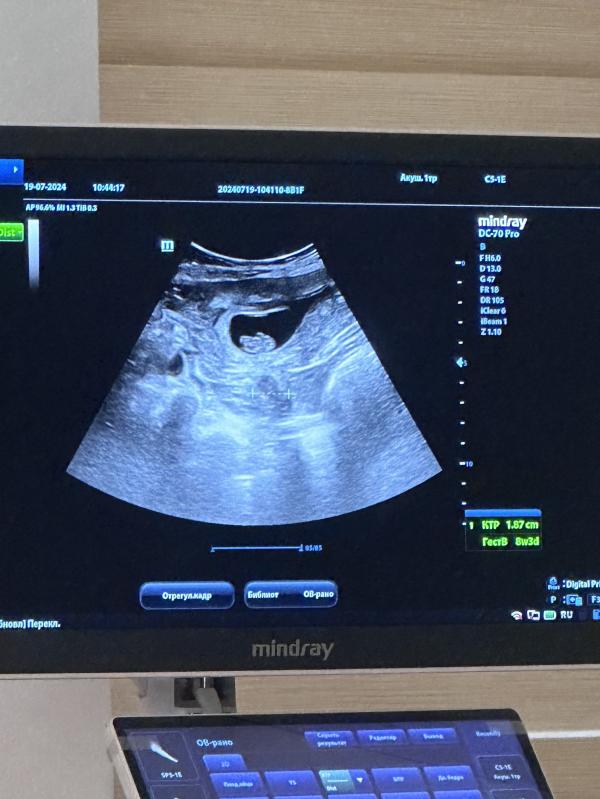

Моя креветочка: фото и немного о ней

Оставлю тут свою креветочку

19.07.2024